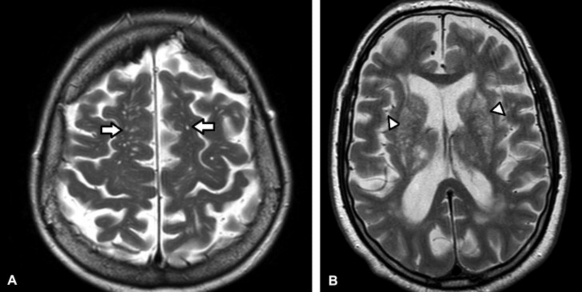

(A-B) RM de cerebro, cortes axiales ponderados en T2. Se objetivan múltiples cavidades milimétricas en los centros semiovales (flechas). Corresponden a dilatación de espacios perivasculares de Virchow-Robin. El etát criblé es consecuencia de la marcada dilatación de numerosos espacios perivasculares en los núcleos grises (cabezas de flecha en b).